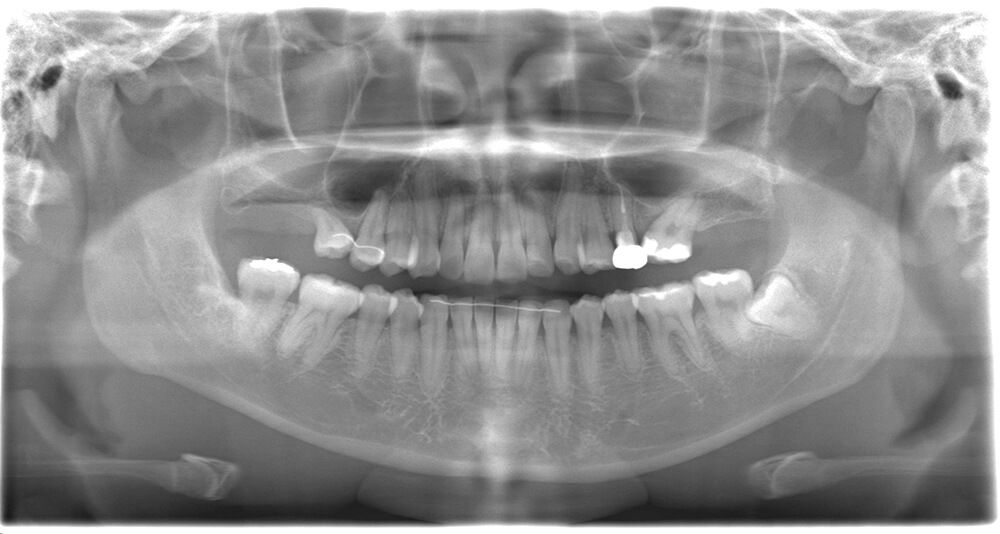

CASE03

Before

After

| 治療期間 | 2年2ヶ月 |

|---|---|

| IPR | なし |

| 治療費 | 1,693,450円 |

| 年齢・性別 | 20代女性 |